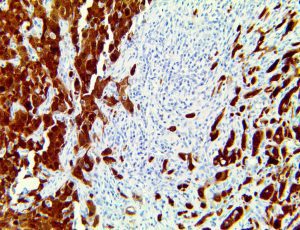

It is the ICU physician who is most likely to witness one of the deadliest manifestations of the abnormal immunological response, the cytokine storm syndrome (CSS). This response is also referred to by some as the cytokine release syndrome (CRS). CSS is characterized by continuous activation and expansion of macrophage and lymphocyte populations, which secrete large amounts of cytokines, causing the cytokine storm. This massive cytokine release is akin to hemophagocytic lymphohistiocytosis (HLH) disease, a syndrome characterized by initial unchecked and persistent activation of cytotoxic T lymphocytes and NK cells.

This activation induces inflammatory monocytes to highly express IL-6, starting a localized and then systemic cascade effect that results in hyperproduction of IL-6, which accelerates the inflammatory process. Because IL-6 also increases vascular permeability, excessive levels cause blood vessels to become very leaky. This, along with clotting factors released from vascular endothelial cells, stimulates the coagulation cascade, resulting in microthrombosis (tiny clots), which leads to ischemia and tissue death of the kidney, intestines, heart, liver, brain and extremities.